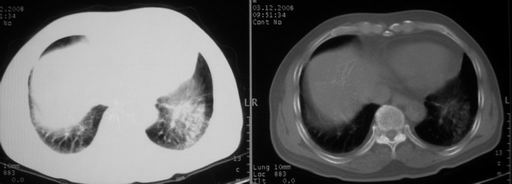

男,78岁,咳嗽、咳痰、发热入院,抗炎治疗一周后已退热,咳血似痰。

10月3日片: